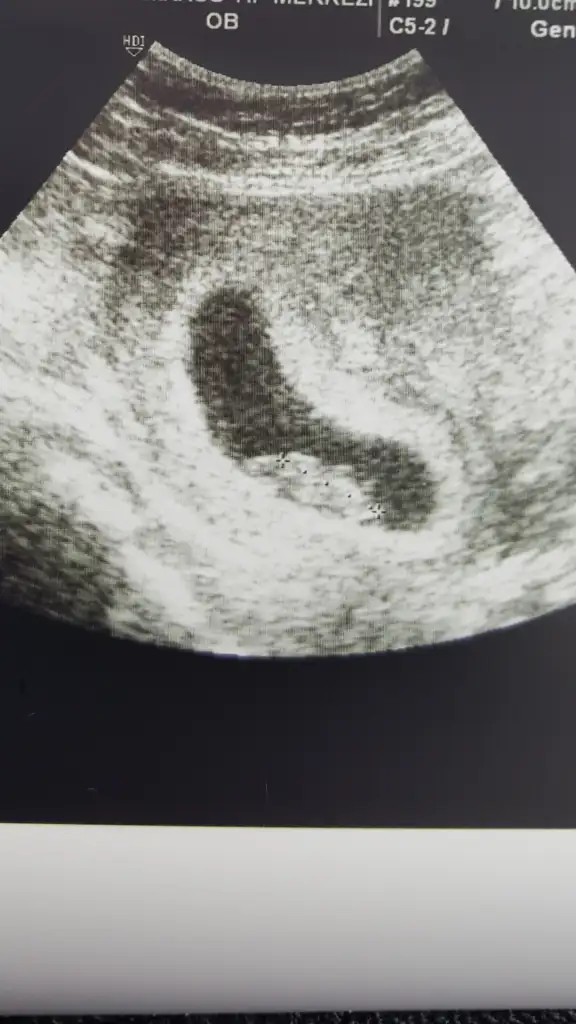

Merhabalar 🤚 doktorunuzdan bir türlü sıra bulamadık maalesef, inşallah bu haftaki randevuda öğrenebiliriz, bu arada 15 haftalık olduk, herhalde artık söyler cinsiyeti diye tahmin ediyorum, çünkü meraktan patlayacağım artık neredeyse 😊😊

Merhabalar. İlgilendiğiniz için çok teşekkürler. Ekteki de 13 haftalık usg görüntüsü ama kordon geçiyor bacak arasından o yüzden dr net birşey söyleyemedi. Yorumunuz var mıdır?